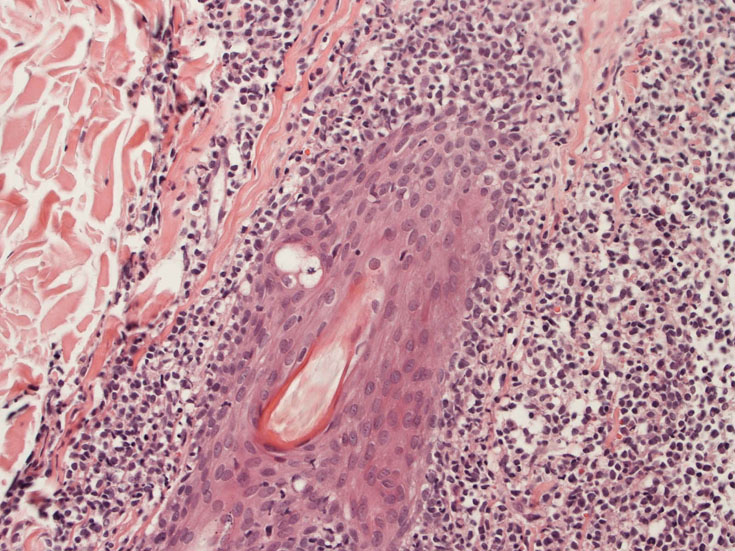

罹患リンパ節の基本構造は消失し腫瘍細胞のびまん性増殖で置換されている。非腫瘍性の小リンパ球(CD3+, CD4/8+)が濾胞様に散在して残る(Fig.01)。不整型または類円形の明るい核をもつmedium-sizeのリンパ球様細胞が密に増殖している。細胞質は乏しい(Fig.02)。CD68陽性macrophageが多く混在する部分が認められた(Fig.03)。

Fig.01Fig.02Fig.03